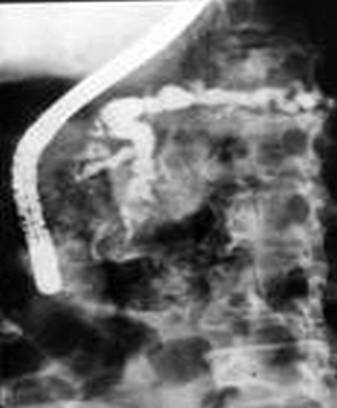

n вирсунготомия эндоскопическая, операционная (редкоприменяемое вмешательство, вследствие технической сложности и редкости стеноза вирсунгова протока изолированно в его устье), ЭПСТ

n панкреатоеюностомия:

а) продольная (Пестова-Джильсби)

б) терминальная (Дюваля)